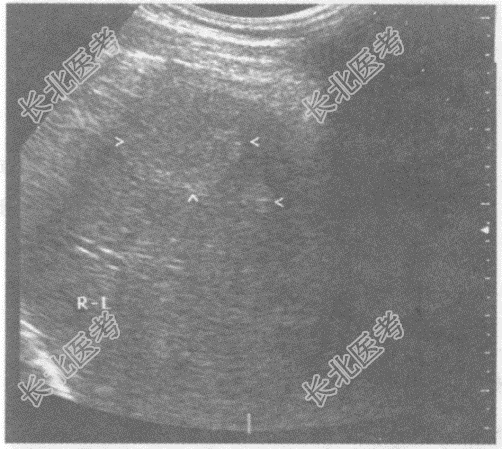

- 单项选择题临床资料:女, 30岁,常规体检。

超声综合描述: 肝右叶可见4.4cm×3.0cm增强回声区,边界清晰.内回声不均。

根据超声提示: A、肝血管瘤